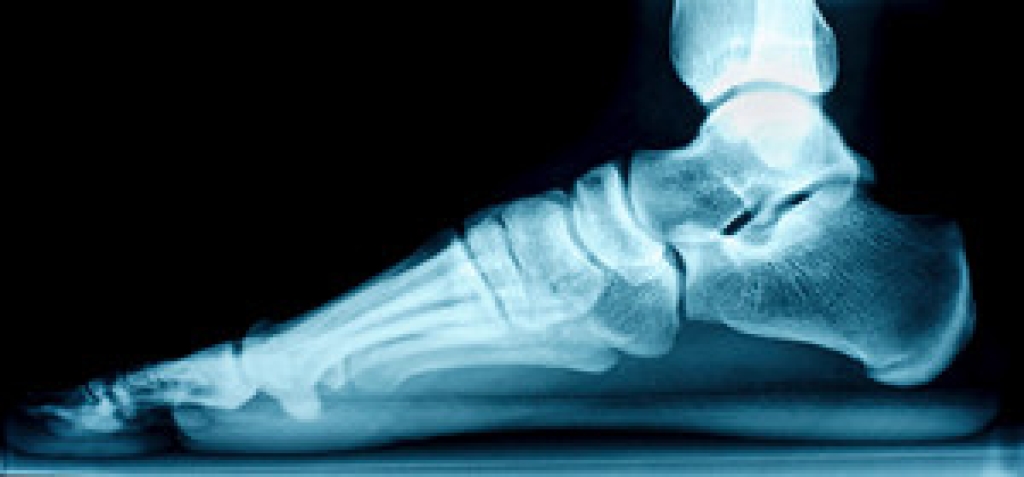

Fallen Arches and How They Affect the Feet

Many people have flat feet from birth, however, flat feet can also be acquired later in life. Years of wear and tear on the feet can lead to a weakening of the tendon that runs along the inside of the ankle and creates the arch in your foot. This is known as having fallen arches. Unlike congenital flat feet, which typically cause no symptoms, flat feet due to fallen arches can be painful. If you have fallen arches, you may feel pain in your heel or arch areas and see swelling along the inside of the ankle. Wearing supportive shoes and custom orthotics, as well as stretching the feet can help you manage fallen arch pain. If you have painful fallen arches, it is suggested that you see a podiatrist for treatment.

Flatfoot is a condition in which the arch of the foot is depressed and the sole of the foot is almost completely in contact with the ground. About 20-30% of the population generally has flat feet because their arches never formed during growth.